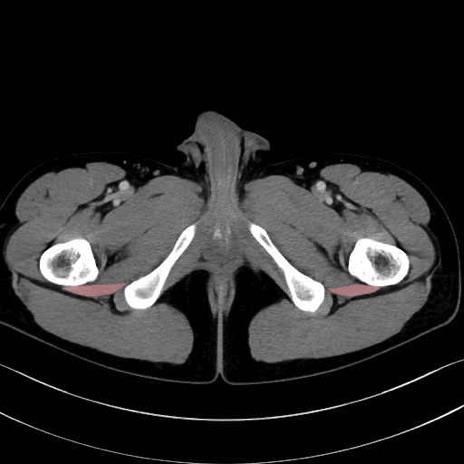

大腿方形筋 (Quadratus femoris)